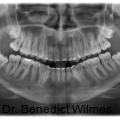

Miniimplantate im anterioren Gaumen werden aufgrund ihrer einfachen Insertion, Vielseitigkeit und der sehr hohen Verlässlichkeit immer beliebter. Der anteriore Gaumen ist aufgrund seiner guten Knochendichte und der meist geringen Mukosadicke ein sicherer Insertionsort, da zudem auch das Risiko einer Wurzelverletzung minimal ist. Fotos: © Prof. Dr. Benedict Wilmes